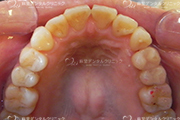

ホワイトニングや審美歯科治療後の素敵な笑顔です。

ただし、歯ぐきの写真などを気持ち悪く感じる方は、あまり見ないでくださいね。